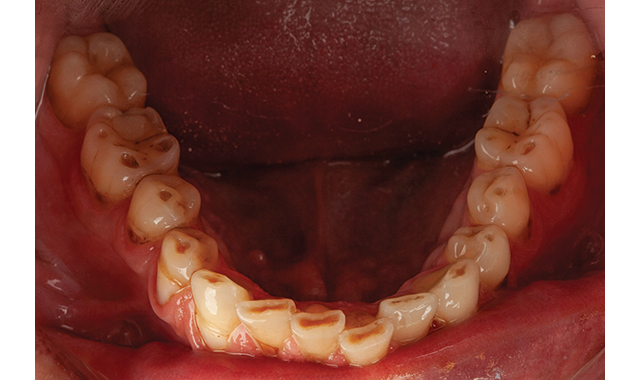

[Fig. 1] Using a DSLR camera with studio lighting allows dentists to focus on the details of a failing system and to confidently offer treatment options.

This can be as simple as using an intraoral camera or, for higher quality presentation, a digital single-lens reflex (DSLR) camera with refined lighting (Fig. 1). In case presentation, the higher the quality, the better. Make no mistake about it: Dentistry is a big-ticket item. Think about the presentation that expensive products use to target and attract customers.